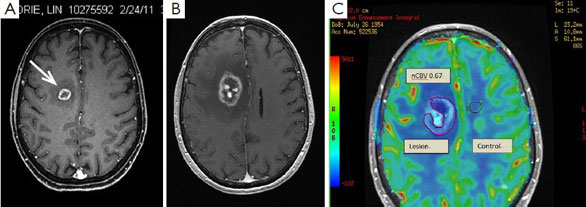

放射性壞死是放射線引發(fā)的腦組織慢性炎癥損傷,臨床上表現(xiàn)不太明顯。許多患者沒(méi)感覺(jué)有什么異常,只是在做磁共振成像檢查時(shí)偶然發(fā)現(xiàn)的。

↑ 放射性壞死

圖片來(lái)源:http://vit.tpkit.ru

放射性壞死與腦轉(zhuǎn)移瘤難以區(qū)分

腦放射性壞死的另一個(gè)麻煩是,與腦轉(zhuǎn)移瘤復(fù)發(fā)難以區(qū)分。腦腫瘤由于缺乏血管,中心往往也有明顯的壞死區(qū),這就讓影像科醫(yī)生犯了難——究竟是放射導(dǎo)致的壞死,還是轉(zhuǎn)移癌復(fù)發(fā)了?

對(duì)醫(yī)生來(lái)說(shuō),這兩種情況表現(xiàn)出的癥狀差不多,臨床上也難以鑒別。對(duì)患者來(lái)說(shuō),無(wú)論是放射性壞死誤診為腦腫瘤,還是腫瘤誤診為壞死,都是不可接受的,前者引起過(guò)度治療,后者則會(huì)貽誤病情。

怎么辦呢?我們需要有經(jīng)驗(yàn)的影像科醫(yī)生幫忙,有時(shí)還需要使用PET掃描來(lái)鑒別。